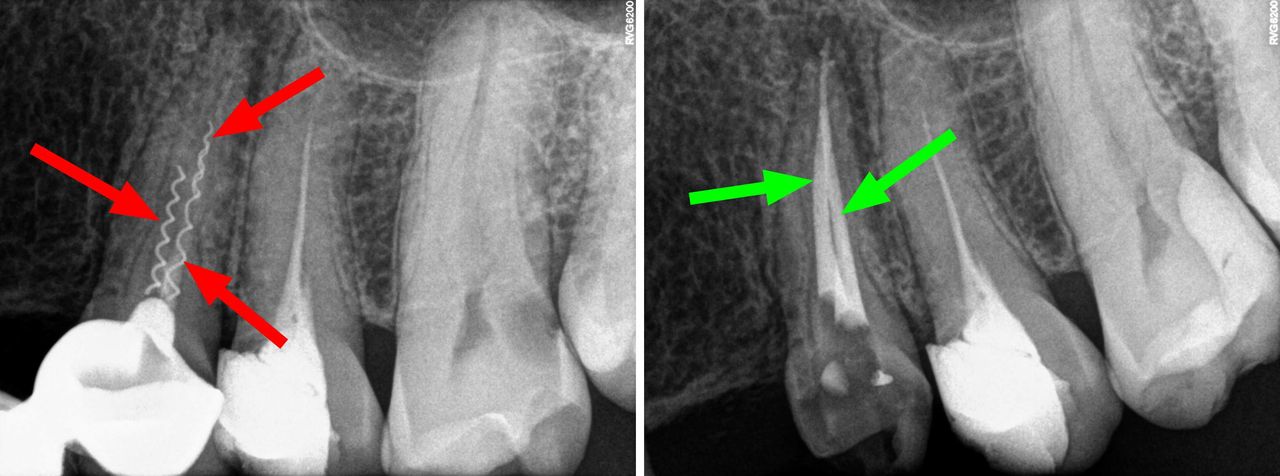

- Usuwanie złamanych narzędzi kanałowych oraz innych ciał obcych pozostawionych w kanałach korzeniowych

- Specjalizujemy się w powtórnym leczeniu kanałowym i leczeniu powikłań co oznacza, że mamy wieloletnie doświadczenie w usuwaniu złamanych instrumentów kanałowych w szybki, bezbolesny i nieinwazyjny sposób. Dr Gończowski jest autorem specjalistycznego zestawu mikroinstrumentów (FRS®) przeznaczonych do usuwania ciał obcych z kanałów korzeniowych